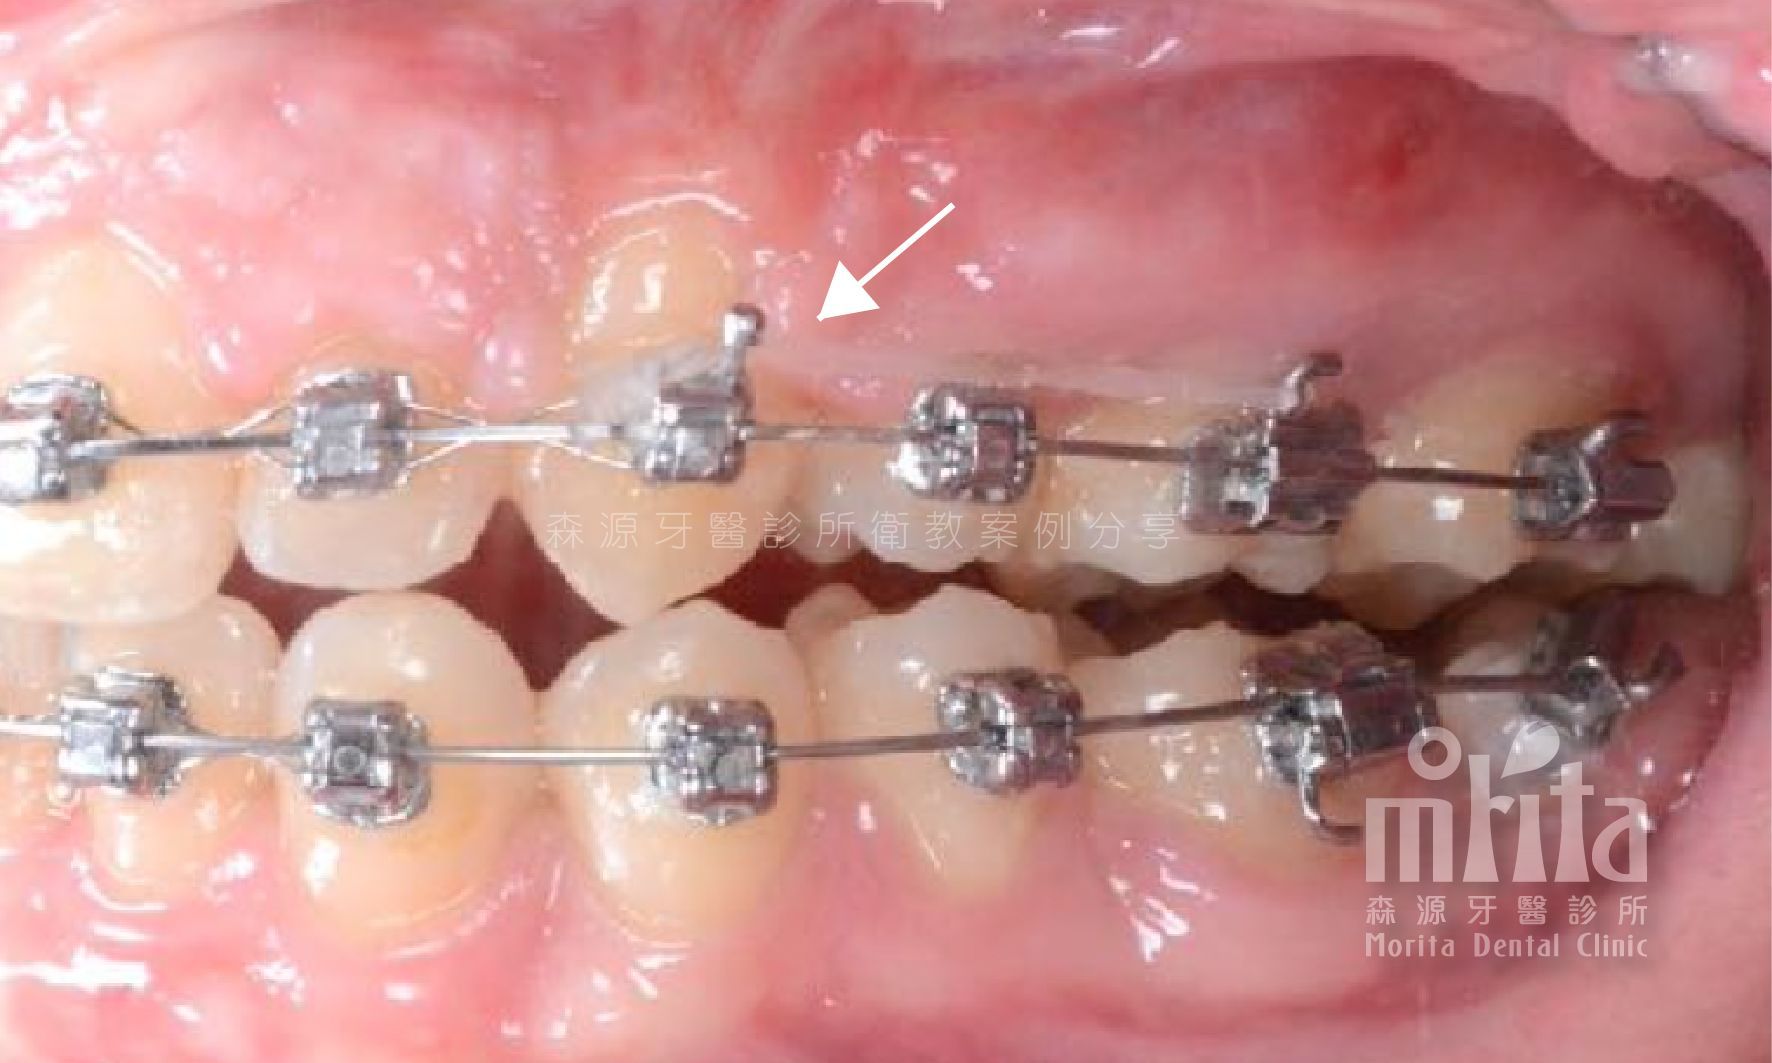

可能因為過早地缺牙,可能因為齒列過於擁擠,又或是老天爺開的玩笑,造成有些該⻑出來的牙齒⻑不出來,需要在阻生齒還有生⻑潛力時拉一把,讓牙齒順利萌發。

阻生齒 Impaction